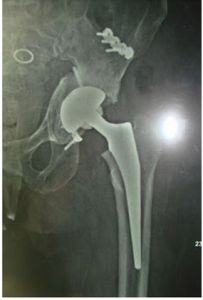

4.術後24小時內常規拍X線片,檢查人骨頭在髖臼內的位置,也便於術後隨診比較。

6.嚴格定期隨診(術後1、2、3、6、12月以及以後每年),以便指導鍛鍊和了解情況。定期攝X線片檢查,以便早期發現併發症,如有疼痛、炎症,應查找原因,及時處理。X線片檢查應注意觀察有無骨與骨水泥、與柄間透亮帶,柄折斷,骨水泥折斷,柄端與髓腔內側的關係,假體下沉,股骨距吸收,股骨上端內側骨水泥裂開,骨質吸收等